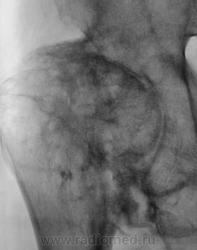

И вторичные выраженные деформирующие изменения на фоне двусторонней дисплазии суставов. Хондроматоз суставов

Наверное, в основе дисплазия (никогда такой не видел), но и об остеоартропатии мысль есть. Предполагаю заболевание спинного мозга.

Пациент в течение 3 лет самостоятельно не передвигается, основное положение - лежа.

сирингомиелия?

Наиболее вероятен диспластический генез коксартроза.

Последствия болезни Пертеса?